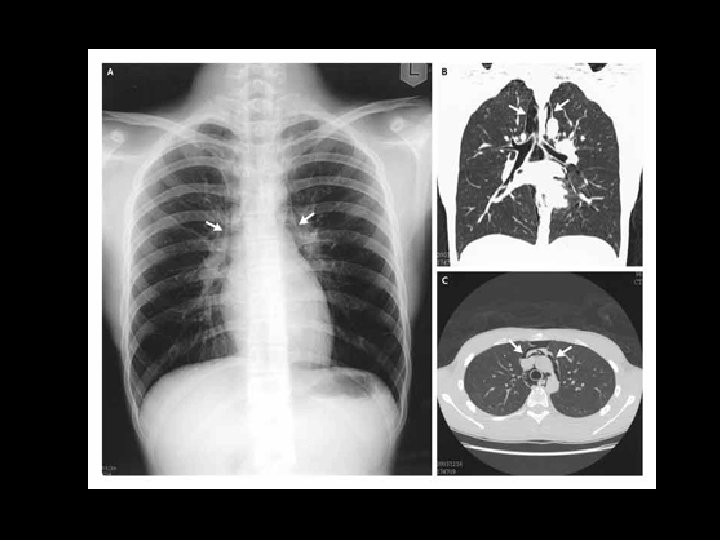

Heimildir n n Moore KL, Dalley AF. Clinically oriented anatomy. Lippincott Williams and Wilkins. Canada, 1999. http: //content. nejm. org/cgi/content/full/354/11/1177/F 1 http: //www. emedicine. com/ped/topic 1832. htm Sobotta, atlas der Anatomie des Menschen